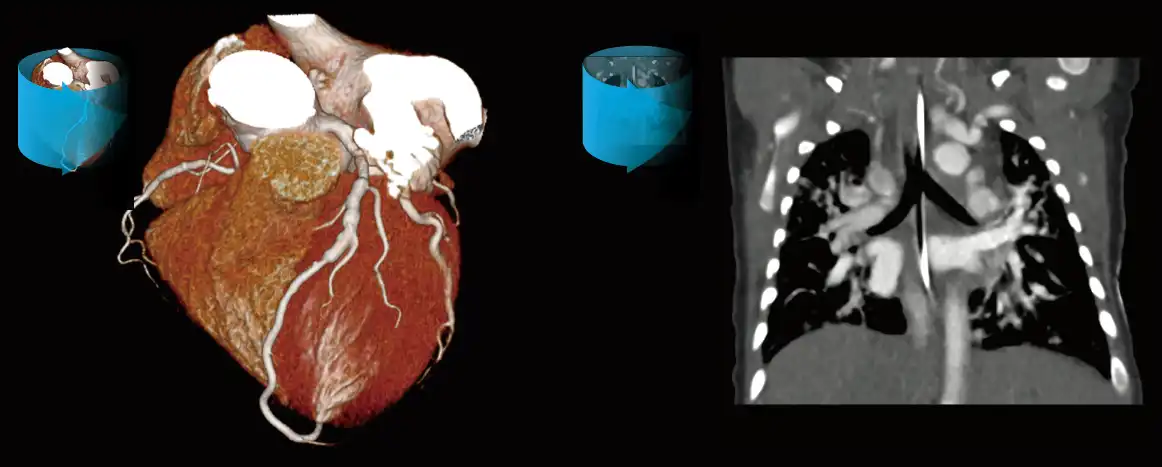

GENESIS Edition’s 16 cm wide area detector signicantly improves your ability to obtain high-quality images for routine and advanced studies. One rotation is all it takes to acquire a whole heart, a neonatal chest, a foot or an ankle exam – in a fraction of a second with less dose and great z-axis uniformity.

Adding dynamic functional imaging to morphology can provide valuable further insights, helping you to optimize disease management and treatment plans. Advanced perfusion maps can assist in diagnosis and therapy response verification of stroke or tumors, while dynamic joint studies help identify causes of pain or immobility.